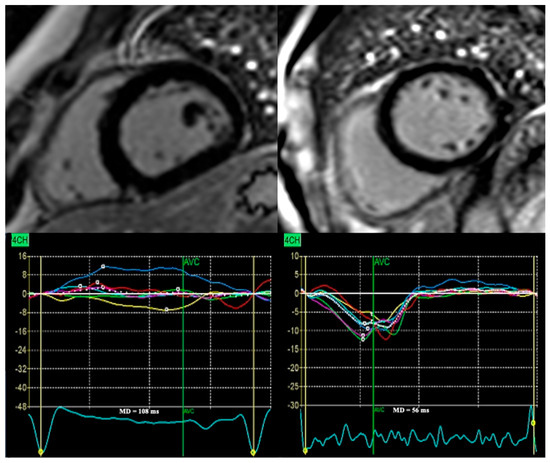

Mechanical Dispersion in Dilated and Non-Dilated Left Ventricular Cardiomyopathy: A New Frontier in Arrhythmic Risk Prediction

Background: Sudden cardiac death (SCD) is a major challenge in dilated (DCM) and non-dilated left ventricular cardiomyopathy (NDLVC). Current management strategies, based on left ventricular ejection fraction (LVEF), the presence or extent of myocardial scar, and selected high-risk genetic variants, are insufficient to [...] Read more.

Background: Sudden cardiac death (SCD) is a major challenge in dilated (DCM) and non-dilated left ventricular cardiomyopathy (NDLVC). Current management strategies, based on left ventricular ejection fraction (LVEF), the presence or extent of myocardial scar, and selected high-risk genetic variants, are insufficient to accurately identify patients at risk. Mechanical dispersion (MD), derived from speckle-tracking echocardiography, is a potential marker of arrhythmic risk that reflects variability in regional myocardial contraction timing. Aim: The purpose of this narrative review is to synthesize current evidence on the predictive role of MD for ventricular arrhythmias (VA) and SCD in DCM and NDLVC, with particular emphasis on its relationship to myocardial fibrosis (MF) and established echocardiographic markers. Results: Across prospective and retrospective cohorts of DCM patients, increased MD has consistently identified individuals at higher arrhythmic risk, often independently of LVEF and global longitudinal strain (GLS). Reported threshold values for risk prediction range from 50 ms to 90 ms, with hazard ratios confirming incremental prognostic accuracy. The relationship between MD and MF assessed by late gadolinium enhancement (LGE) on cardiac magnetic resonance (CMR) remains uncertain: some patients experience VA in the absence of LGE, while others display elevated MD despite no detectable focal MF, suggesting that additional mechanisms contribute to the arrhythmogenic substrate in DCM and NDLVC. Conclusions: MD may enhance SCD risk stratification in DCM and NDLVC by reflecting components of the arrhythmic substrate that are not detected by conventional markers. Full article